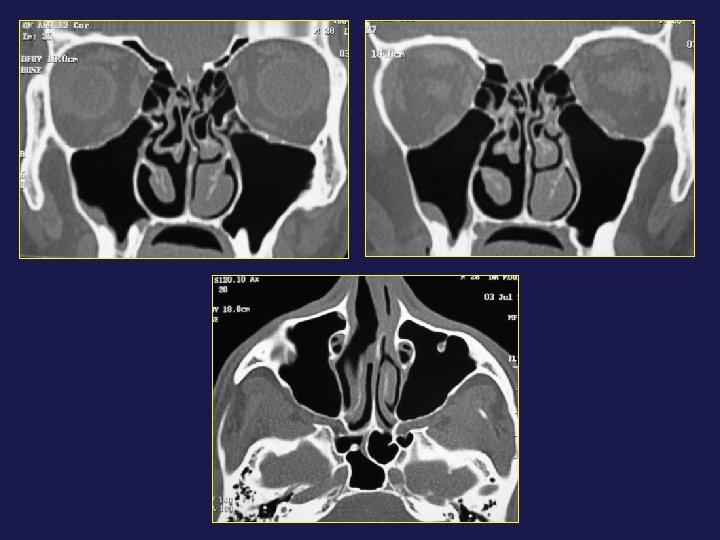

→ Hémorragie : lésion artère éthmoïdale antérieure

→ Orbite : hématome

Cellule d’Onodi → Atteinte du nerf optique

→ Fuite de LCR : brèche osseuse

→ Fuite de LCR : déhiscence osseuse